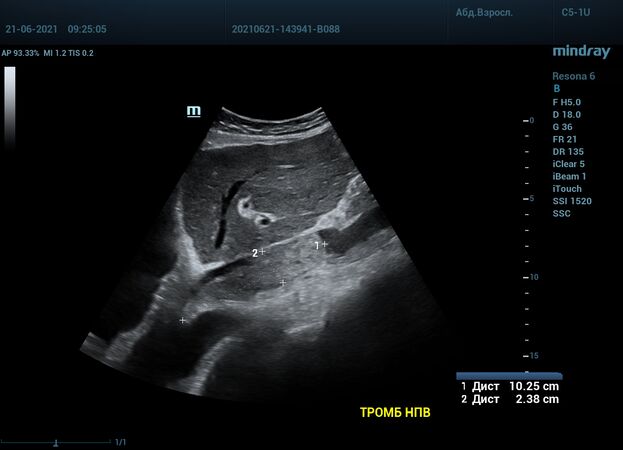

Интересный случай из практики нашего врача-аппликатора. Использовался экспертный ультразвуковой прибор Mindray Resona 6, стандартные заводские пресеты и автоматическая оптимизация iTouch. В эхокардиографии всегда помогает колорайзинг, чаще всего используется оранжевый оттенок. Пациент обследуется перед оперативным лечением по поводу онкологии почки. Вены нижних конечностей у данного пациента без особенностей, сжимаемы и проходимы. Казалось бы, проблема тромбоза миновала но в процессе эхокардиографического исследования, при сканировании нижней полой вены в субкостальном сечении, определяется эхогенное образование. Образование на месте просвета нижней полой вены. Вена расширена, эхогенное включение проникает в правое предсердие. По краю тромба в цветопотоковой визуализации определяется кровоток. Онкологическое заболевание почки осложнилось тромбозом почечной вены, с распространением тромба в нижнюю полую вену и правое предсердие. Изюминку добавляет то, что в других эхокардиографических сечениях тромб совершенно не виден.